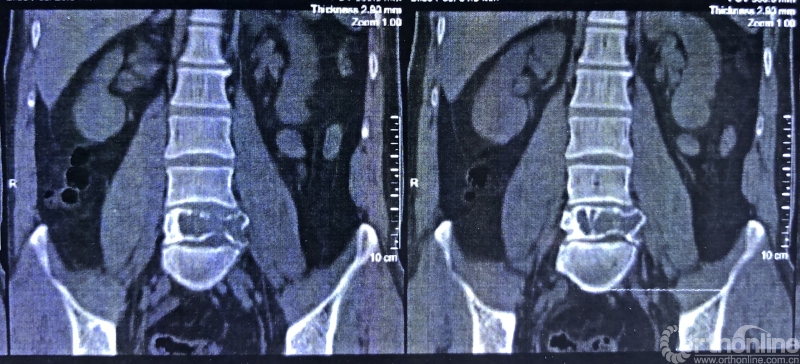

就诊前CT

通过对患者详细的身体检查、穿刺活检和综合评估后,确诊患者是腰椎骨巨细胞瘤,第五腰椎破坏70%以上,邻近软组织也有破坏。这种肿瘤属于交界性的有恶性倾向的良性肿瘤,若不彻底切除,患者疼痛会逐渐加剧,甚至因骨质坍塌而瘫痪,若肿瘤细胞转移更会危及生命。若是能在早期尽快彻底、完全地切除肿瘤及被侵蚀椎体,病人才很可能完全战胜肿瘤。

术前CT三维重建